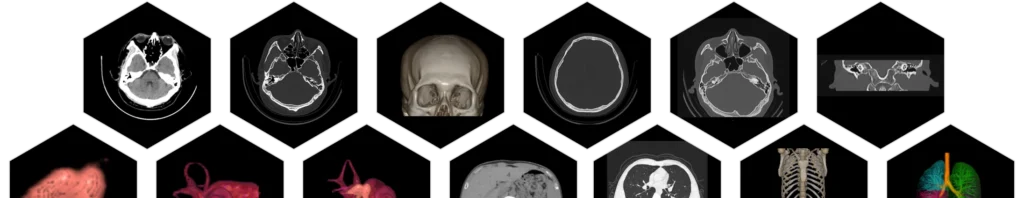

• Intelligente Nachbearbeitung:

» Automatische Erkennung von Organen und Läsionen.

» Segmentierung.

» Messung und Überwachung.

• Intelligente Diagnostik:

» Früherkennung von COVID-19

» Automatische Diagnose und Überwachung von Lungenrundherden

» Beurteilung von Lungenemphysem

» Verbesserte diagnostische Effizienz und Zuverlässigkeit